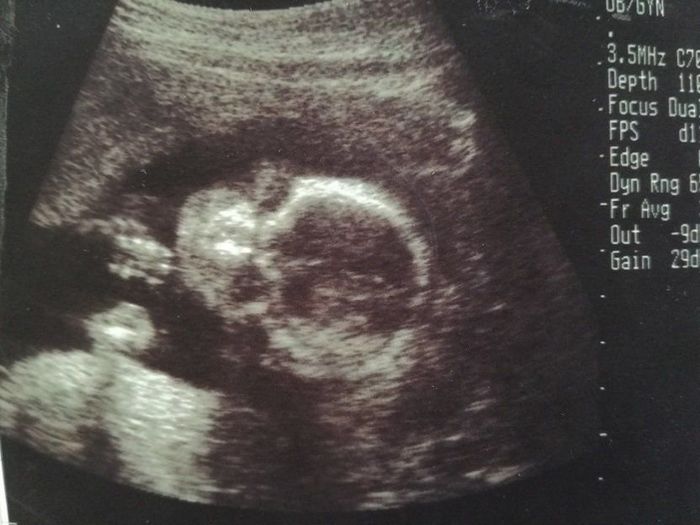

妊娠12週目のエコー写真

上の二つの画像は、同じ日に撮ってもらったもの。人の形になっている赤ちゃんの姿を確認して、体に衝撃が走りました。エコー画像上で、小さい体をモゾモゾと動かしている様子も見られて、本当にかわいらしく、感動して少し目が潤んでしまいました。人の姿として確認できる画像でしたので、夫に見せても、実家に帰省して両親に見せても、みんな「おぉー!」と喜びの声を上げていました。